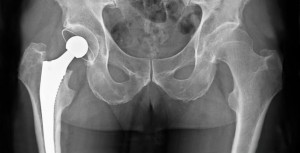

¿Cuánto tiempo dura un reemplazo de cadera? ¿Y el de rodilla?